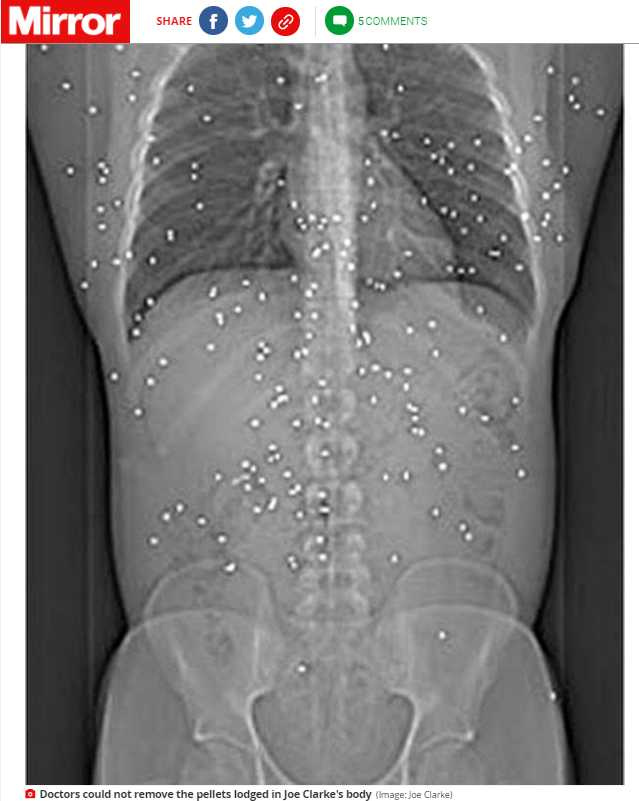

2007年12月某天,克拉克在家中突然聽到敲門聲,於是他打開門查看,沒想到竟然被歹徒拿槍掃射,嚇得他馬上往屋內跑,而在那次的事件後,他的背部就充滿了千瘡百孔,甚至有150粒子彈卡在他的體內無法取出,重點是,克拉克並沒有因為中槍死亡,反倒是奇蹟般地活了下來。

克拉克雖倖存,但醫生經過評估後,發現若要取出他體內的子彈太過危險,所以就讓他帶著150粒子彈一起生活直到今天;15年過去,克拉克認為這些子彈深深影響到他的生活,對他的健康造成毀滅性的影響,他說:「我不敢相信我的生命會就這樣結束,就是不斷地與子彈抗爭。」

▼克拉克帶著50顆子彈生活。(圖/CTWANT/翻攝自《鏡報》)

克拉克與子彈共存這15年來,已經動了20次手術,還必須定期接受X光檢查,確保子彈沒有移動到會危及他生命的位置,而他也因為槍擊案患上的關節炎,他說:「它在慢慢地殺死我,有時候我真希望當時沒有活下來,他們奪走我曾經的生活,奪走我的所有。」